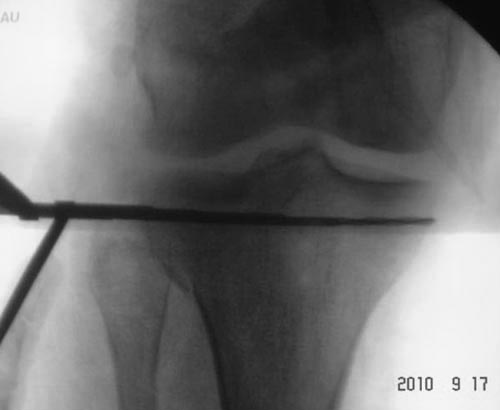

Всем доброго времени суток! Мужчина, 36 лет, импрессионный перелом медиального (внутреннего) мыщелка ББК левой ноги. С его слов обстоятельства травмы: Прыгнул с высоты около 3м и при приземлении подвернул ногу.

Прилагаю снимки ренген + КТПодскажите пожалуйста, какой фиксатор подойдет для данного перелома.

Снимки сделаны на вытяжении?

Вытяжение не делалось.

Ренген - это первичные снимки сразу после поступления, после чего дежурный наложил гипс.

КТ - уже в гипсе.

Переломы тибиал плато по Schatzker IV характерны импрессией суставной поверхности без вовлечения медиального кортекса. Из исследований стандартные снимки и КТ. Снимки на вытяжении рекомендуются только при переломах с вовлечением двух мыщелков, а при переломе одного из мыщелков отсутствует укорочение и вытяжение не требуется.